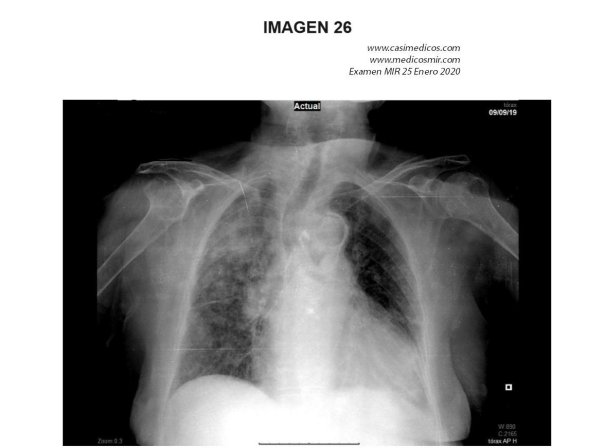

Pregunta 26

Mujer de 90 años con antecedentes de enfermedad de Alzheimer en estadio terminal (Global Deterioration Scale 7), dependencia para todas las actividades básicas de la vida diaria y disfagia ocasional a líquidos. Acude a urgencias por presentar en las últimas horas delírium hipoactivo, taquipnea, taquicardia rítmica y temperatura axilar de 37,3°C. La exploración física es dificultosa y no aporta más datos destacables. Ante la radiografía de tórax que se muestra, ¿cuál es el diagnóstico más probable?:

- Tromboembolismo pulmonar.

- Edema agudo de pulmón.

- Neumonía intersticial aguda.

- Neumonía broncoalveolar aguda.

Respuesta correcta: IMPUGNO

En una persona con demencia grave o terminal con disfagia, la causa más común es una broncoaspiración, siendo la neumonitis química o neumonía aspirativa su consecuencia principal. Por lo que yo la impugnaría

En caso de que no se impugnara finalmente sería la 4, como bien dice